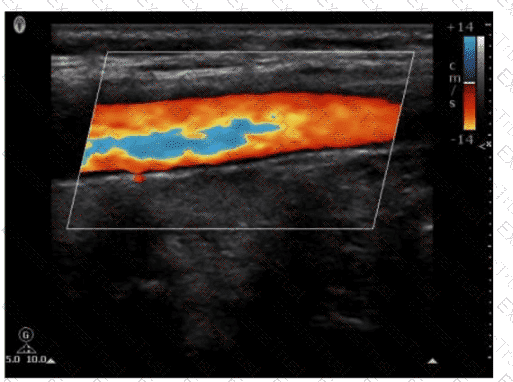

Which adjustment resulted in the change from image A to image B?

Options:

A.

Increased transmit frequency

B.

Increased scale

C.

Decreased color gain

D.

Decreased acoustic power

Question 31

Which pulsed-wave Doppler adjustment would be appropriate to correct the aliasing seen in this image?

Increase the spectral Doppler gain.

Decrease the spectral Doppler gain.

Increase the Doppler pulse repetition frequency.

Decrease the Doppler pulse repetition frequency.